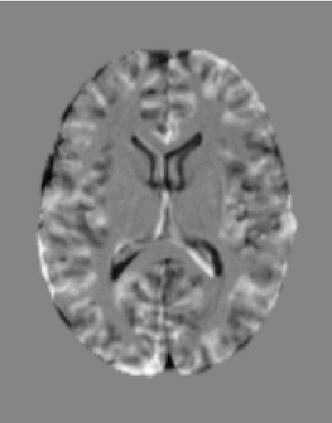

The purpose of this work is to contribute to the state of the art of deep-learning methods for diffeomorphic registration. We propose an adversarial learning LDDMM method for pairs of 3D mono-modal images based on Generative Adversarial Networks. The method is inspired by the recent literature for deformable image registration with adversarial learning. We combine the best performing generative, discriminative, and adversarial ingredients from the state of the art within the LDDMM paradigm. We have successfully implemented two models with the stationary and the EPDiff-constrained non-stationary parameterizations of diffeomorphisms. Our unsupervised and data-hungry approach has shown a competitive performance with respect to a benchmark supervised and rich-data approach. In addition, our method has shown similar results to model-based methods with a computational time under one second.